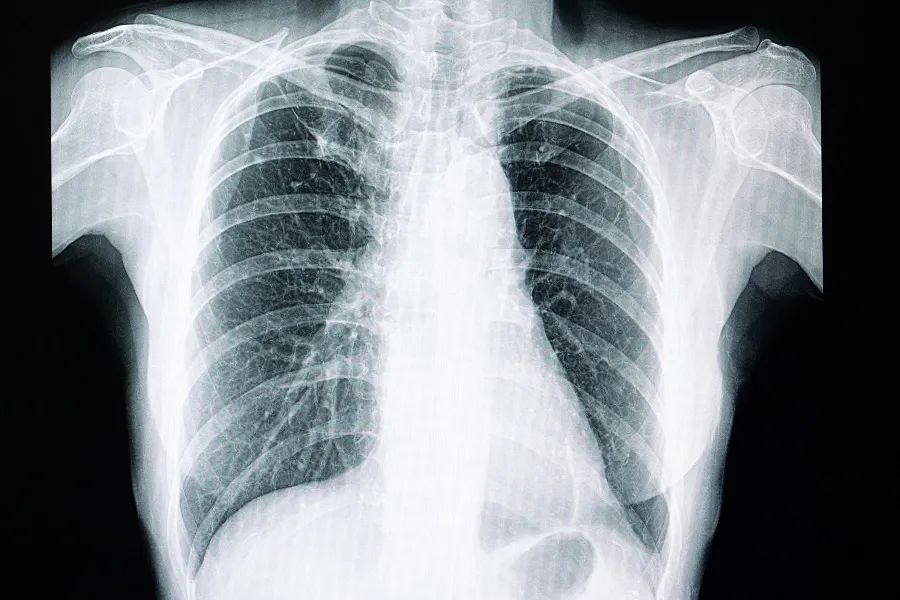

那如何区分良性结节与恶性结节?其实,医生是需要综合各项检查来进行评估的。

肺结节为恶性的危险因素有:年长、吸烟、有恶性肿瘤史、结节直径大、边缘不规则、位置在肺上叶、随访过程中结节增长、活检结果提示可疑恶性[1-3]。

一、高危人群每年CT筛查

年龄≥40岁[1]且具有以下任一危险因素的,都是高危人群:

(1) 吸烟或曾经吸烟≥ 20包/年(或400支/年)且戒烟时间<15年;

(2) 有环境或高危职业暴露史(如石棉、铍、铀、氡等接触者);

(3) 合并慢阻肺、弥漫性肺纤维化或既往有肺结核病史者;

(4) 得过恶性肿瘤或有肺癌家族史的。此外,还需考虑被动吸烟、烹饪油烟以及空气污染等因素。